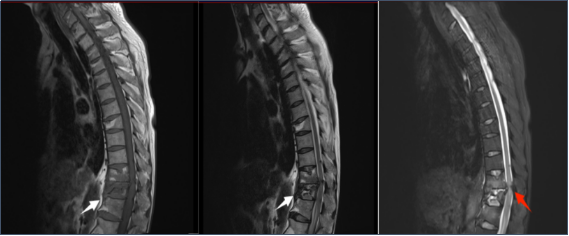

辅助检查:

从磁共振初步考虑:胸腰椎骨质破坏伴双下肢不全瘫:结核?布鲁菌感染?因患者有瘫痪症状,病情进展,骨质破坏严重,我们为患者充分评估后进行手术治疗,清除感染病灶及脊柱内固定等,术后送病检培养结果证实为布鲁氏菌感染。该患者诊断为:布鲁氏菌脊柱炎(胸11-1)伴双下肢不全瘫。该患者腰痛是由布鲁氏菌引起的脊柱炎症和骨质破坏,这是一种比较少见的疾病。